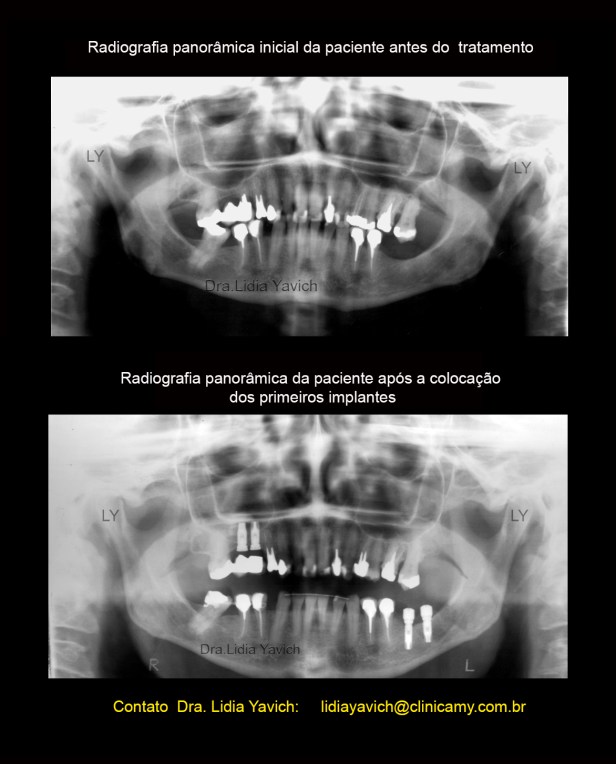

Ao exame radiográfico obseva-se ausência dos elementos dentais 18,16,28,28,36, 46 4 48.

Os elementos 15, 14, 22, 24, 26, 35,44 e 45 se encontram endodonticamente tratados.

Presença de prótese fixa com apoio nos elementos 16/15. Presença de prótese fixa unitária com pino metálico intracanal nos elementos 14, 22, 26, 35,34 e 45.

Extensa restauração coronária nos elementos 13,24 e 44.

Presença de material restaurador nos elementos 11, 21, 23, 27,32 e 47.

Perda óssea alveolar na maxila e na mandíbula mais acentuada nas áreas edêntulas.

Alongamento do processo estiloide esquerdo.

Foi planejada a instalação de dois implantes no lado esquerdo inferior e dois implantes no lado direito superior onde a paciente tinha uma prótese velha.

Radiografias panorâmicas comparativas: inicial antes do tratamento em oclusão habitual e a panorâmica com os implantes colocados, com o DIO, dispositivo intraoral em posição neuromuscular fisiológica instalado em boca.